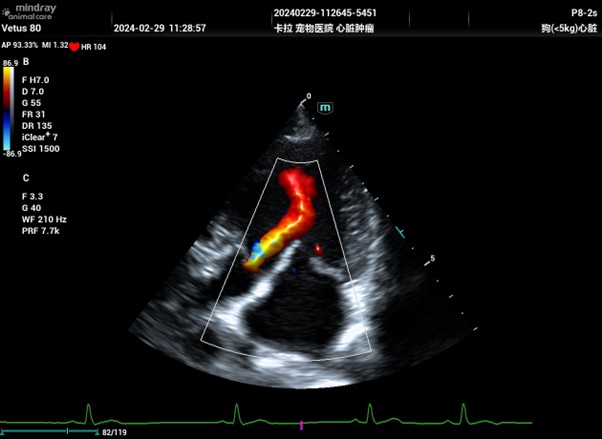

Colour Doppler image from Mindray Vetus 80 showing aortic regurgitation

This is what most people think of when you say Doppler and is generally just called Colour Doppler (CF) though can also be referred to as Colour Flow Doppler (CFD) and/or Colour Doppler Imaging (CDI). It is displayed as a colour overlay in a window over a B-mode (or M-mode) image. It is not specific for blood flow, though visualising blood flow is the most common use and detects motion relative to the transducer.

When scanning the abdomen of a panting or otherwise wriggling patient, you will notice colour filling the window (known as flash artefact). This is caused by the motion of the tissues relative to the transducer. Colour Doppler can appear very sensitive to different velocities based on how the settings are adjusted, and there are various artefacts that can impede interpretation if not set correctly. It also has a maximum velocity that can be displayed (Nyquist limit) before artefacts are seen.

As shown in the image, the two colours will appear in the direction of motion relative to the probe. The standard setup is; blue away from the probe, red towards the probe and green, in cardiac imaging, which reflects the degree of flow disturbance present.